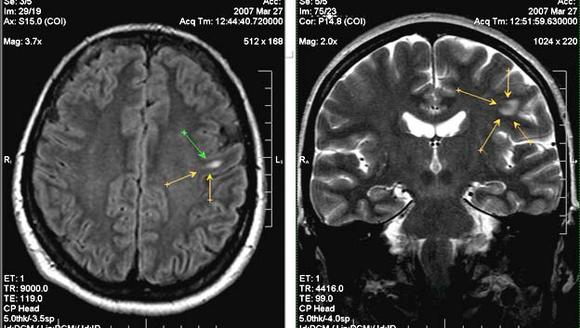

МРТ глиоза головного мозга

Особенности МР-диагностики очаговых изменений вещества мозга

Как правило, о наличии очаговых изменений в веществе мозга становится известно после того, как пациент прошел МРТ. Для уточнения характера поражения и дифференциальной диагностики исследование может быть проведено с контрастированием.

Множественные очаговые изменения более характерны для инфекций, врожденной патологии, сосудистых расстройств и дисметаболических процессов, рассеянного склероза, тогда как единичные очаговые изменения возникают после перенесенных инсультов, перинатальных поражений, отдельных видов травм, метастазировании опухолей.

Магнитно-резонансная томография головного мозга позволяет сосчитать очаги глиоза. Томограммы показывают структуру участков. Чем обширнее фокус, тем больше клинических симптомов повреждения ЦНС.

Динамическое обследование (повторное МРТ) позволяет оценить увеличение размеров очагов головного мозга.

С помощью МРТ и КТ удается рассчитать количество нейроглиальных разрастаний на единицу объема церебральной ткани. Величина используется для оценки прогрессирования заболевания, оценки эффективности лечения.

Диагностика глиоза головного мозга

В большинстве случаев заболевание верифицируется случайно при сканировании головного мозга МРТ или КТ. Опасности формы не представляют. Повторное обследование через несколько месяцев проводится с целью изучения старых глиальных участков. Отсутствие увеличения размеров указывает на благоприятный прогноз.

МР и КТ-ангиография с контрастным веществом помогает выявить сосудистый генез нозологии. Определяет или исключает изменение церебральной активности электроэнцефалография (ЭЭГ). Процедура назначается при появлении эпилептических приступов, мышечных судорогах.